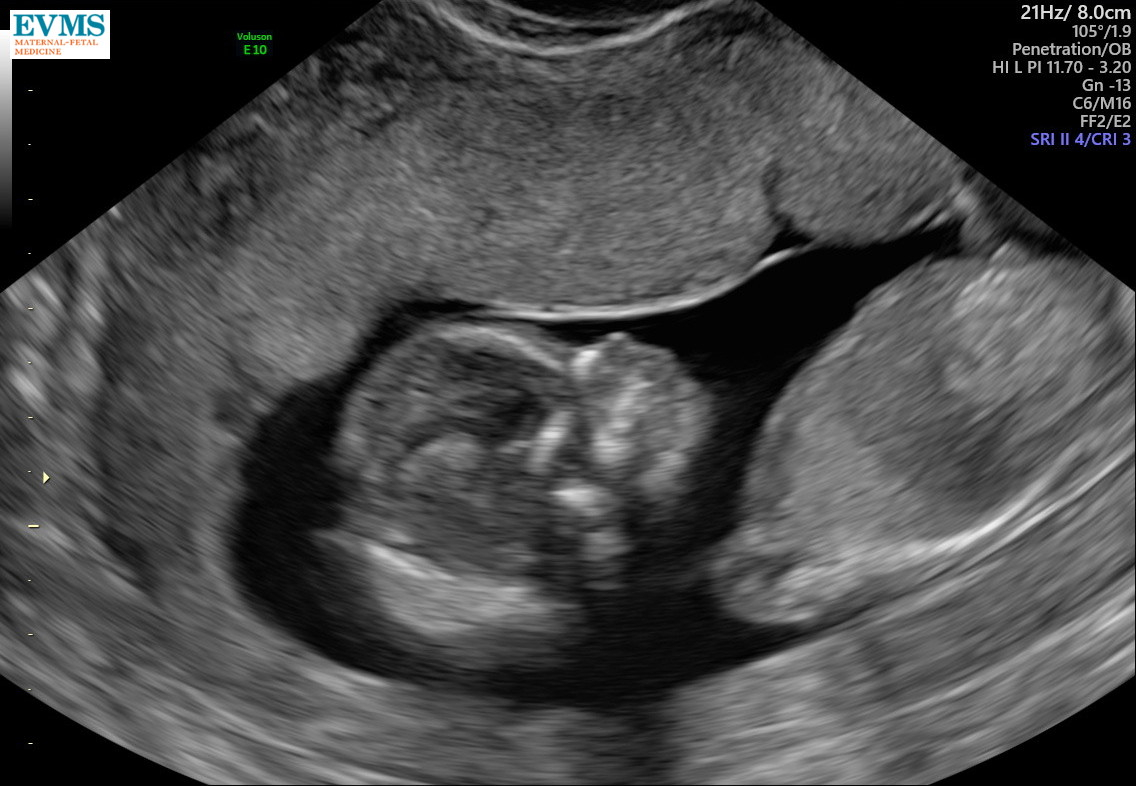

NT scan was normal, heart was 146 BPM. Saw 2 arms, 2 legs, 2 eye sockets, and the brain. Will find out NIPT results and sex by end of next week, hopefully!

NT scan was today - everything looking great! She had the hiccups, it was really funny to see her jump and open her mouth every couple of seconds.